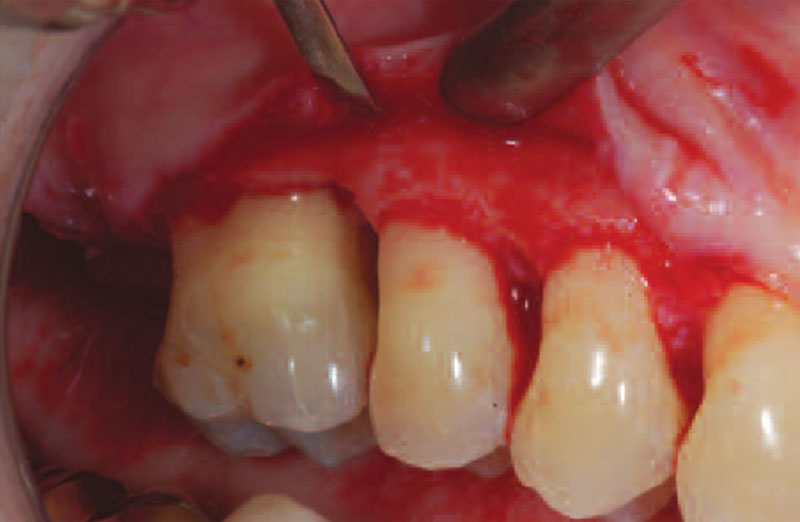

Surgical procedure for treatment of the periodontium. Includes flap elevation for access, guided tissue regeneration (GTR) for narrow and deep intrabony defects, as well as mucogingival procedures for recession and soft tissue corrections around teeth and implants.